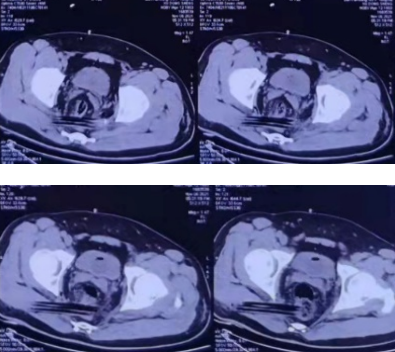

图2CT示木条异物从右侧坐骨大孔穿入、自左侧坐骨大孔穿出

图3、4CT示木条异物与直肠关系密切可能损伤直肠